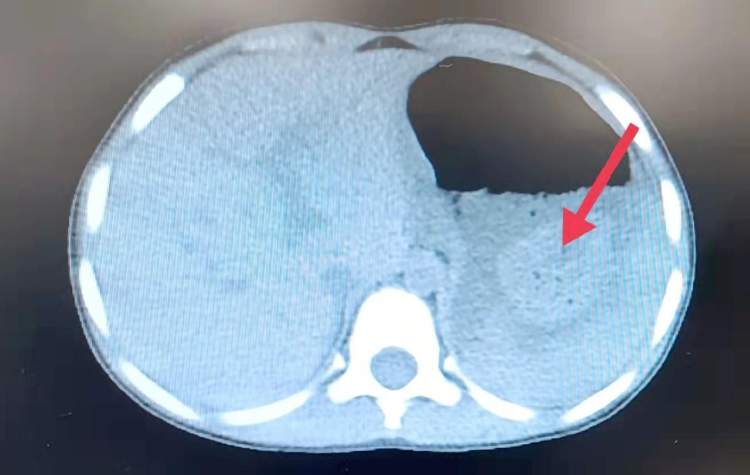

空腹连吃6块柿饼,4岁女童引发腹痛吐血!过量食用柿饼引起巨大胃结石

四岁女童彤彤(化名)因“腹痛、呕血”前往复旦大学附属儿科医院急诊科就诊。据家属介绍,2月14日中午开始,彤彤开始出现上腹部间歇性疼痛、呕吐,呕吐物里开始出现黑色液体。经过仔细询问,医生们才发现,2月13日晚上彤彤跳舞回家后饥饿难耐,一口气空腹连吃了6块柿饼。

消化科治疗团队初步推断:彤彤的胃内异物是过量食用柿饼引起的巨大胃结石!